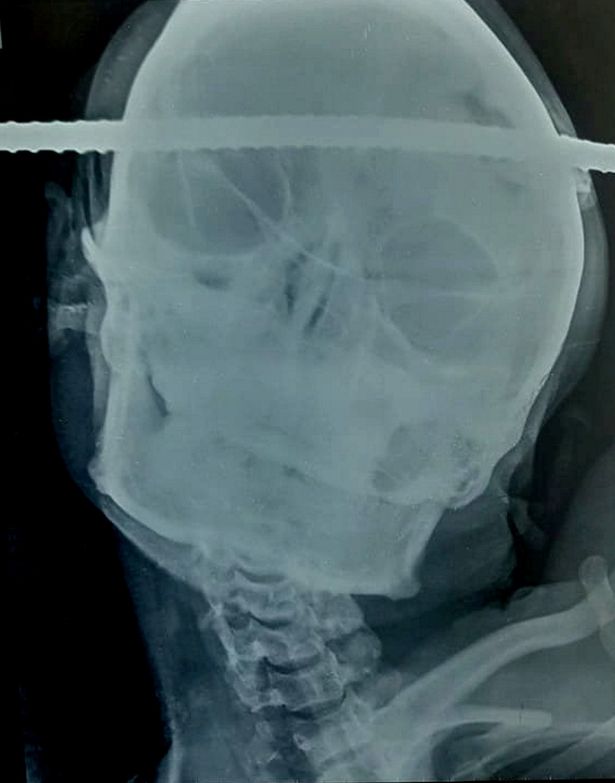

نجا عامل هندي من الموت بأعجوبة، عقب اختراق سيخ حديدي لرأسه، أثناء عمله في موقع بناء وسط الهند.

ووفقا لصحيفة "ديلي ميرور"، سقط سانجاي باهي، البالغ من العمر 21 عاما، أثناء بنائه بئرا ملكا له، متعرضا لاختراق سيخ حديدي لجمجمته، من الجانب الأيمن للأيسر.

ونقل باهي للمستشفى للخضوع لجراحة طارئة، ظل في كامل وعيه طيلة وقتها والتي استمرت 90 دقيقة.

وأضاف الجراح أن السيخ المعدني كان بعيدا ببعض الميلليمترات، عن الأوعية الدموية الرئيسية داخل المخ، المسؤولة عن نقل المعلومات بين الدماغ وأجزاء الجسم.